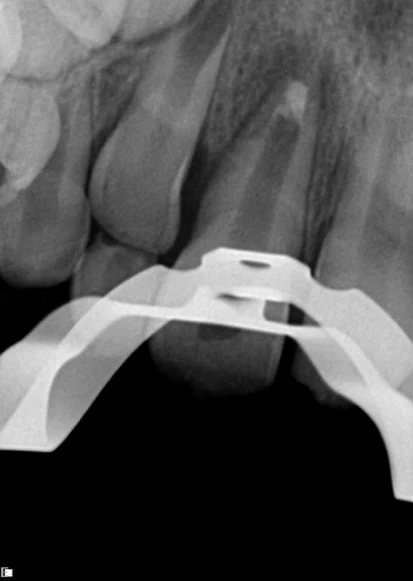

Paciente com 8 anos de idade, compareceu ao consultório com fístula em região vestibular e leve escurecimento em dente 11 (figura 1). Foi realizado o exame clinico e radiográfico (radiografia periapical) na qual foi observado o ápice aberto desse dente (figura 2). No teste de sensibilidade com gás refrigerante o dente apresentou vitalidade negativa.

Logo após realizou-se uma medida aparente com instrumento em posição ou compactador de NiTi em posição (com cursor) (figura 3). Após preparo químico-mecânico, foi utilizado o EDTA (PUI) por 1 minuto. Por fim, foi aplicado um curativo com hidróxido de cálcio (PUI) durante uma semana.